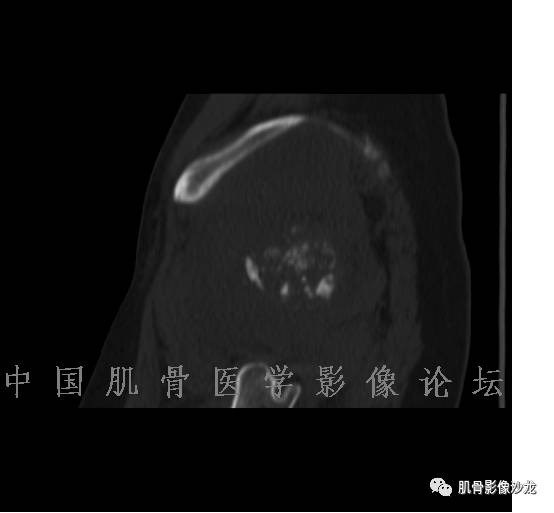

雪舞 : 股骨下端,皮质下偏心性溶骨性破坏,分叶状,T2混杂高信号。无明显软组织肿块。X片未见异常。

雪舞 第一例位置典型,但是限于资料原因,未能明确是否有钙化,周围也未见软组织肿块,骨膜反应

雪舞 :不过T2高信号,分叶状还是要想到软骨肉瘤,毕竟典型位置,骨肿瘤排名第3的软骨肉瘤

飞鹰行动 : 第一列可以看见T2小结节样高信号,周围有纤维组织环绕

高回青 : 另外还可以见到扇贝状分叶

1、软骨肉瘤可以有膨胀性骨质破坏(病例3,4),可以有溶骨性骨质破坏(病例2),局部皮质因为破坏变薄,中断 ;

2、软骨基质T2WI高信号,软骨小叶分叶状,也就会出现高老师提到的骨内膜扇贝形压迹。一般认为骨内膜扇贝形压迹超过骨皮质厚度的2/3是软骨肉瘤在长管状骨的特征性表现。如上图。3、软组织肿块或肿胀;